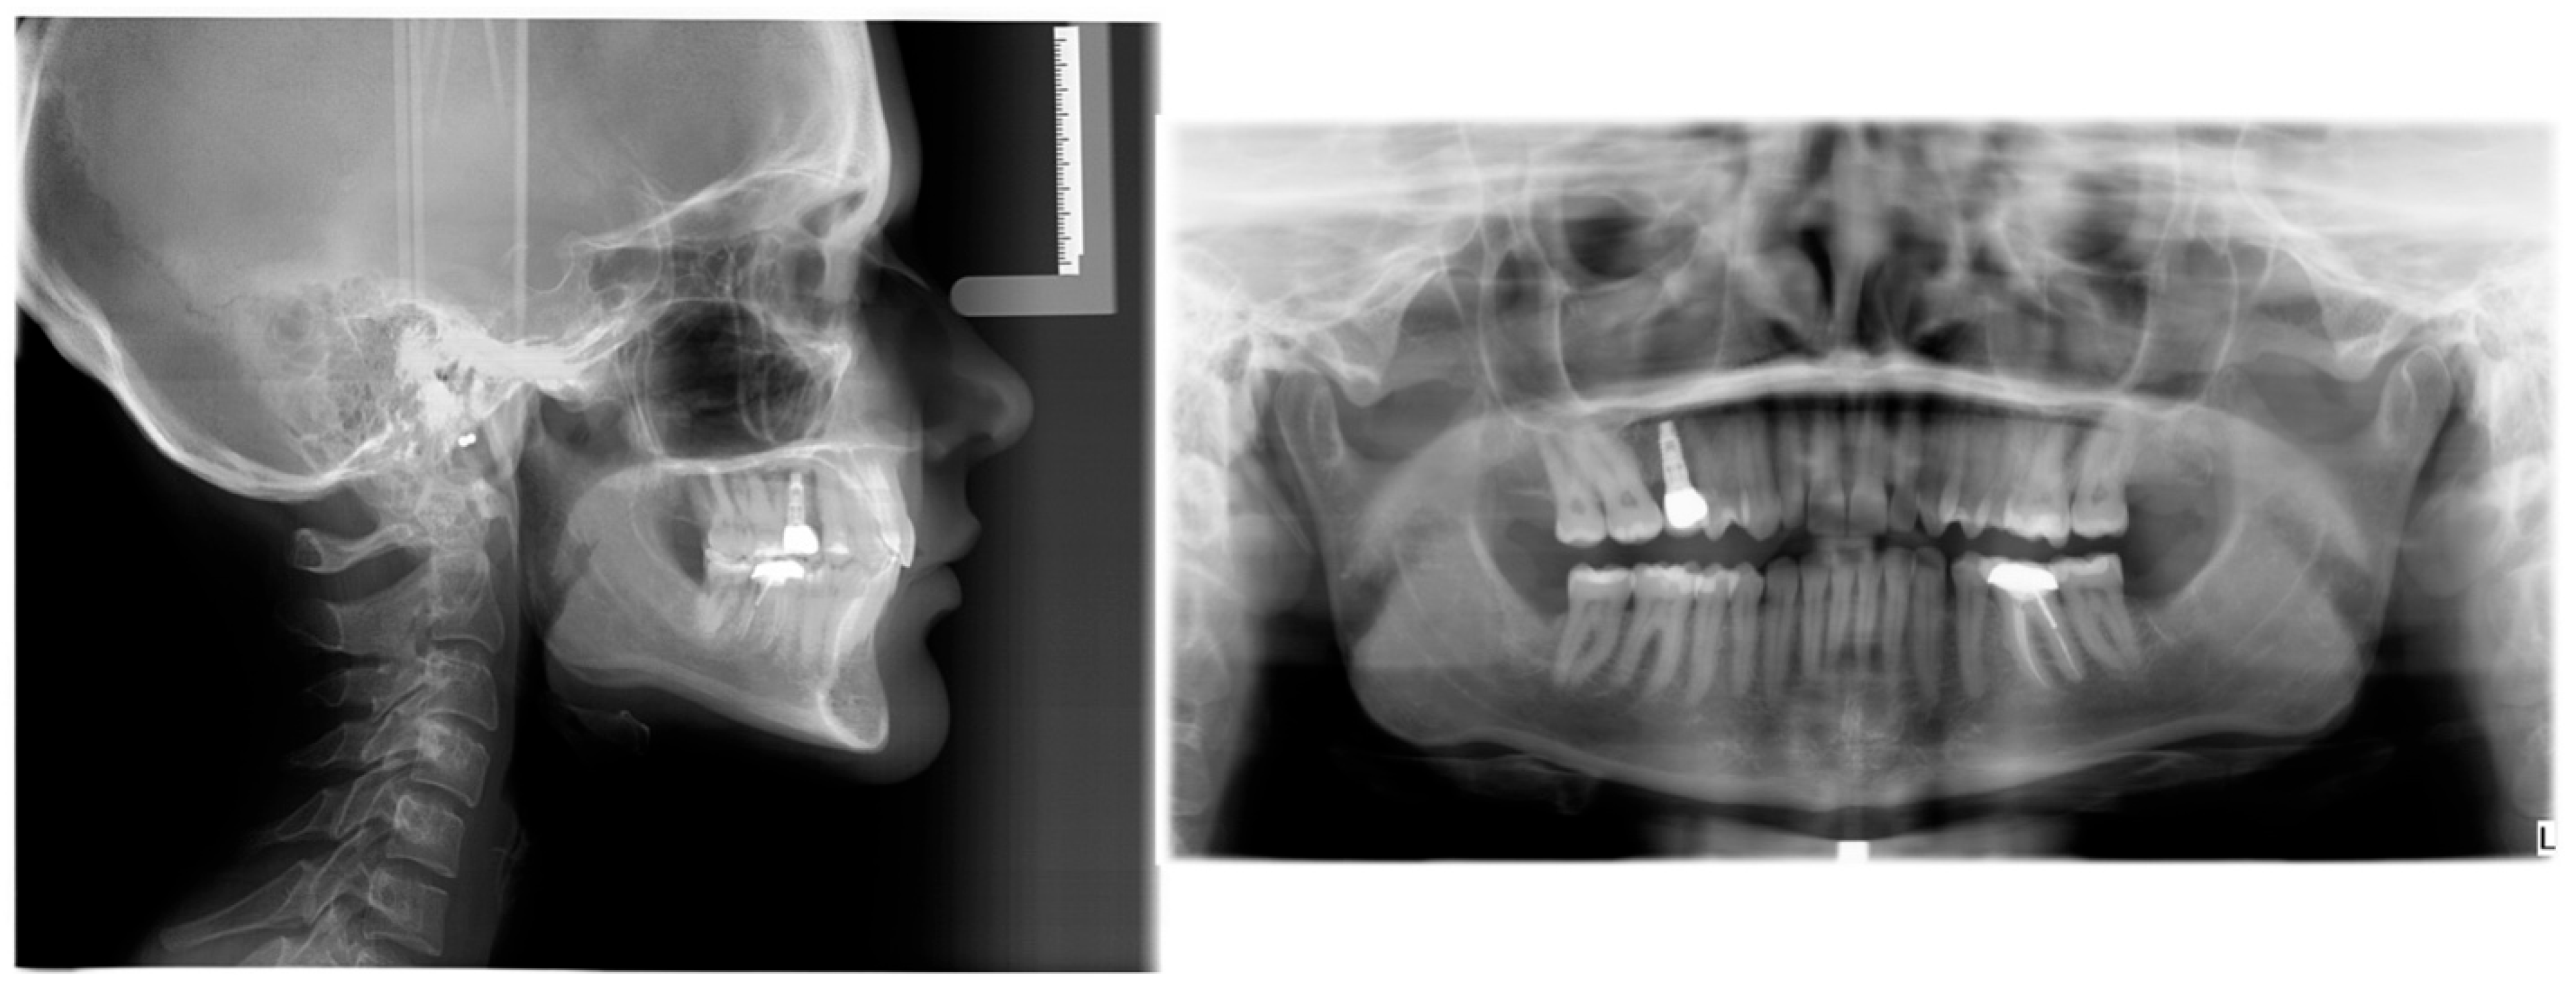

2.1. Pre-Treatment Records and Analysis

2.2. Pre-Treatment Diagnosis